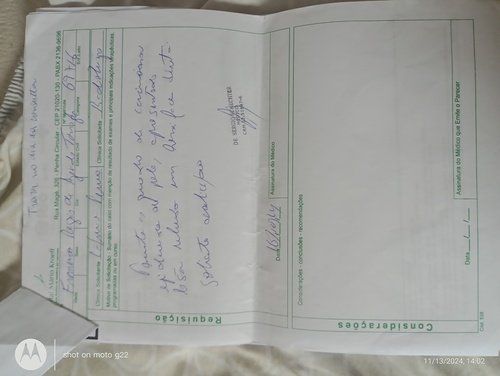

Me chamo Leidiane dos Santos Silva e estou criando essa vaquinha online para ajudar um amigo, pai e muito mais. Ele se chama Francisco Regis de Azevedo Tornaghi. Foi e ainda é uma pessoa que ajuda muitas pessoas e hoje ele está passando por uma fase muito difícil da sua vida. Agora ele está precisando muito da ajuda dos amigos para que ele possa realizar um tratamento de câncer de pele, o qual vem lutando desde o ano passado. Esse ano o câncer voltou e está progredindo de forma muito agressiva. Ele está sendo acompanhado pelo SUS mas o SisReg não dá conta de atender de imediato. Terá que fazer exames muito caros como: análise imunohistoquimico de origem tumoral, tomografia de face, pescoço e tórax. Hoje ele mora em Pedra de Guaratiba e está sendo acompanhado no Hospital MÁRIO KROEFF, na penha, muito longe de casa e fica difícil para a locomoção. Quando começar radioterapia e quimioterapia terá que ir todos os dias. Precisará fazer radioterapia todos os dias e quimioterapia 2 vezes na semana. Para ir de transporte público tem que pegar 4 conduções. Ele não aguenta pois tem 75 anos de idade.Por esse motivo estou aqui fazendo essa vaquinha para que os amigos e familiares possam colaborar com qualquer quantia para ajudar nesse momento muito difícil. Desde já agradeço a todos pela ajuda.